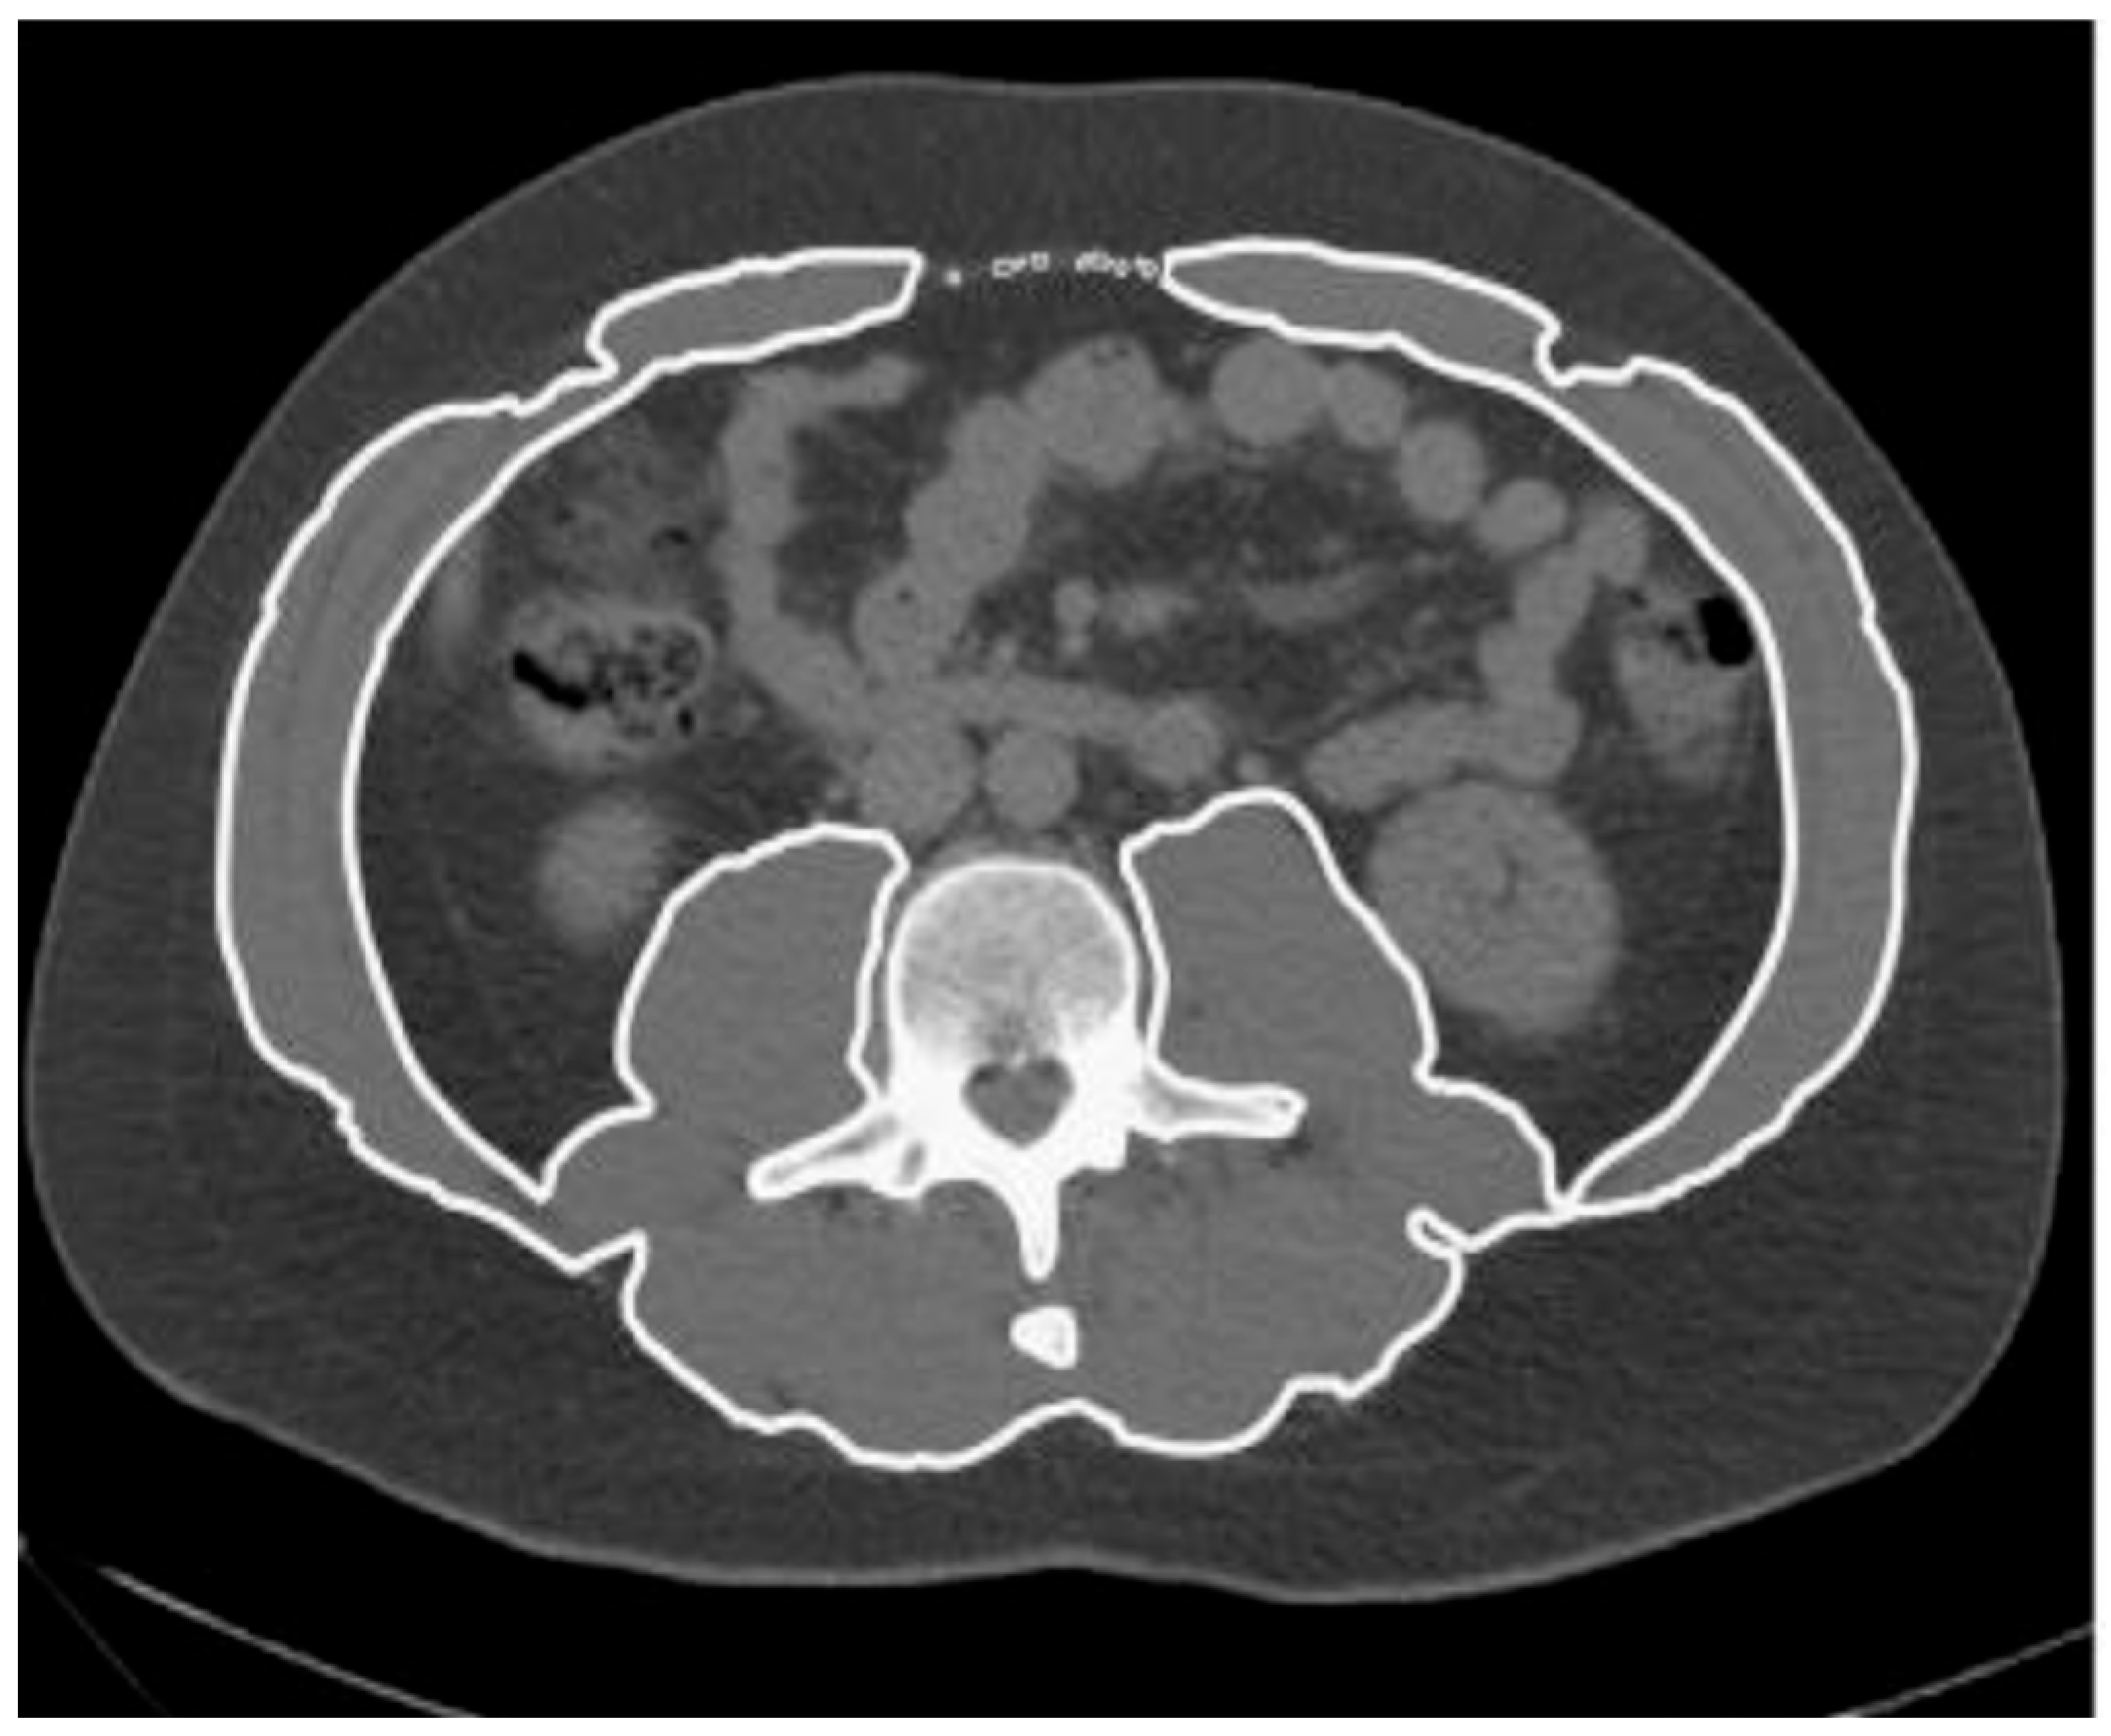

2.2. Image Analysis